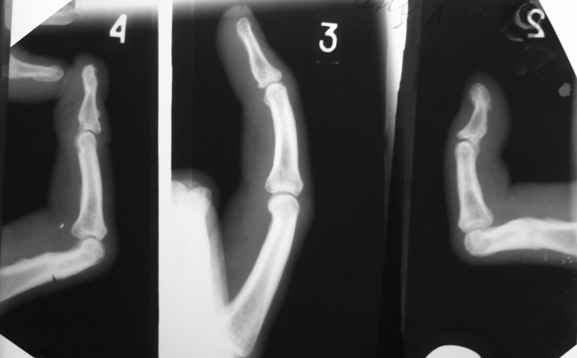

Ограничение движений одинаковое и активных и пассивных. Движения в указанном объеме свободные. Чем вызвано ограничение понять пока не можем. В боковой проекции досняли - получается, что подвывиха нет. Вопросов, в отношении того, что мешает стало еще больше.